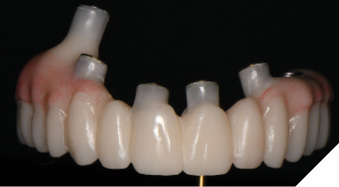

The patient returned 2 weeks from the impressioning appointment for a prototype try in. At this appointment the esthetics, phonetics, soft tissue approximation and occlusion were confirmed. There was no requirement for a verification jig due to the accuracy of the Nexus solution. The restorations were manufactured with milled gold anodized titanium bars overlaid with monolithic zirconia (Figs. 24A-C, 25A-C).

Fig. 24A

Fig. 24B

Fig. 24C

Fig. 25A

Fig. 25B

Fig. 25C